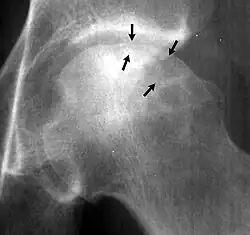

Crescent sign

In radiology, the crescent sign is a finding on conventional radiographs that is associated with avascular necrosis.[1][2][3] It usually occurs later in the disease, in stage III of the four-stage Ficat classification system.[1] It appears as a curved subchondral radiolucent line that is often found on the proximal femoral or humeral head.[1] Usually, this sign indicates a high likelihood of collapse of the affected bone.[1] The crescent sign may be best seen in an abducted (frog-legged) position.[1][4]

The crescent sign is caused by the necrotic and repair processes that occur during avascular necrosis.[1][2] Osteosclerosis occurs at a margin where new bone is placed over dead trabeculae.[1] When the trabeculae experience stress leading to microfractures and collapse, the crescent sign appears.[1]

The crescent sign may be seen with other bone diseases, such as shear fractures.[1]